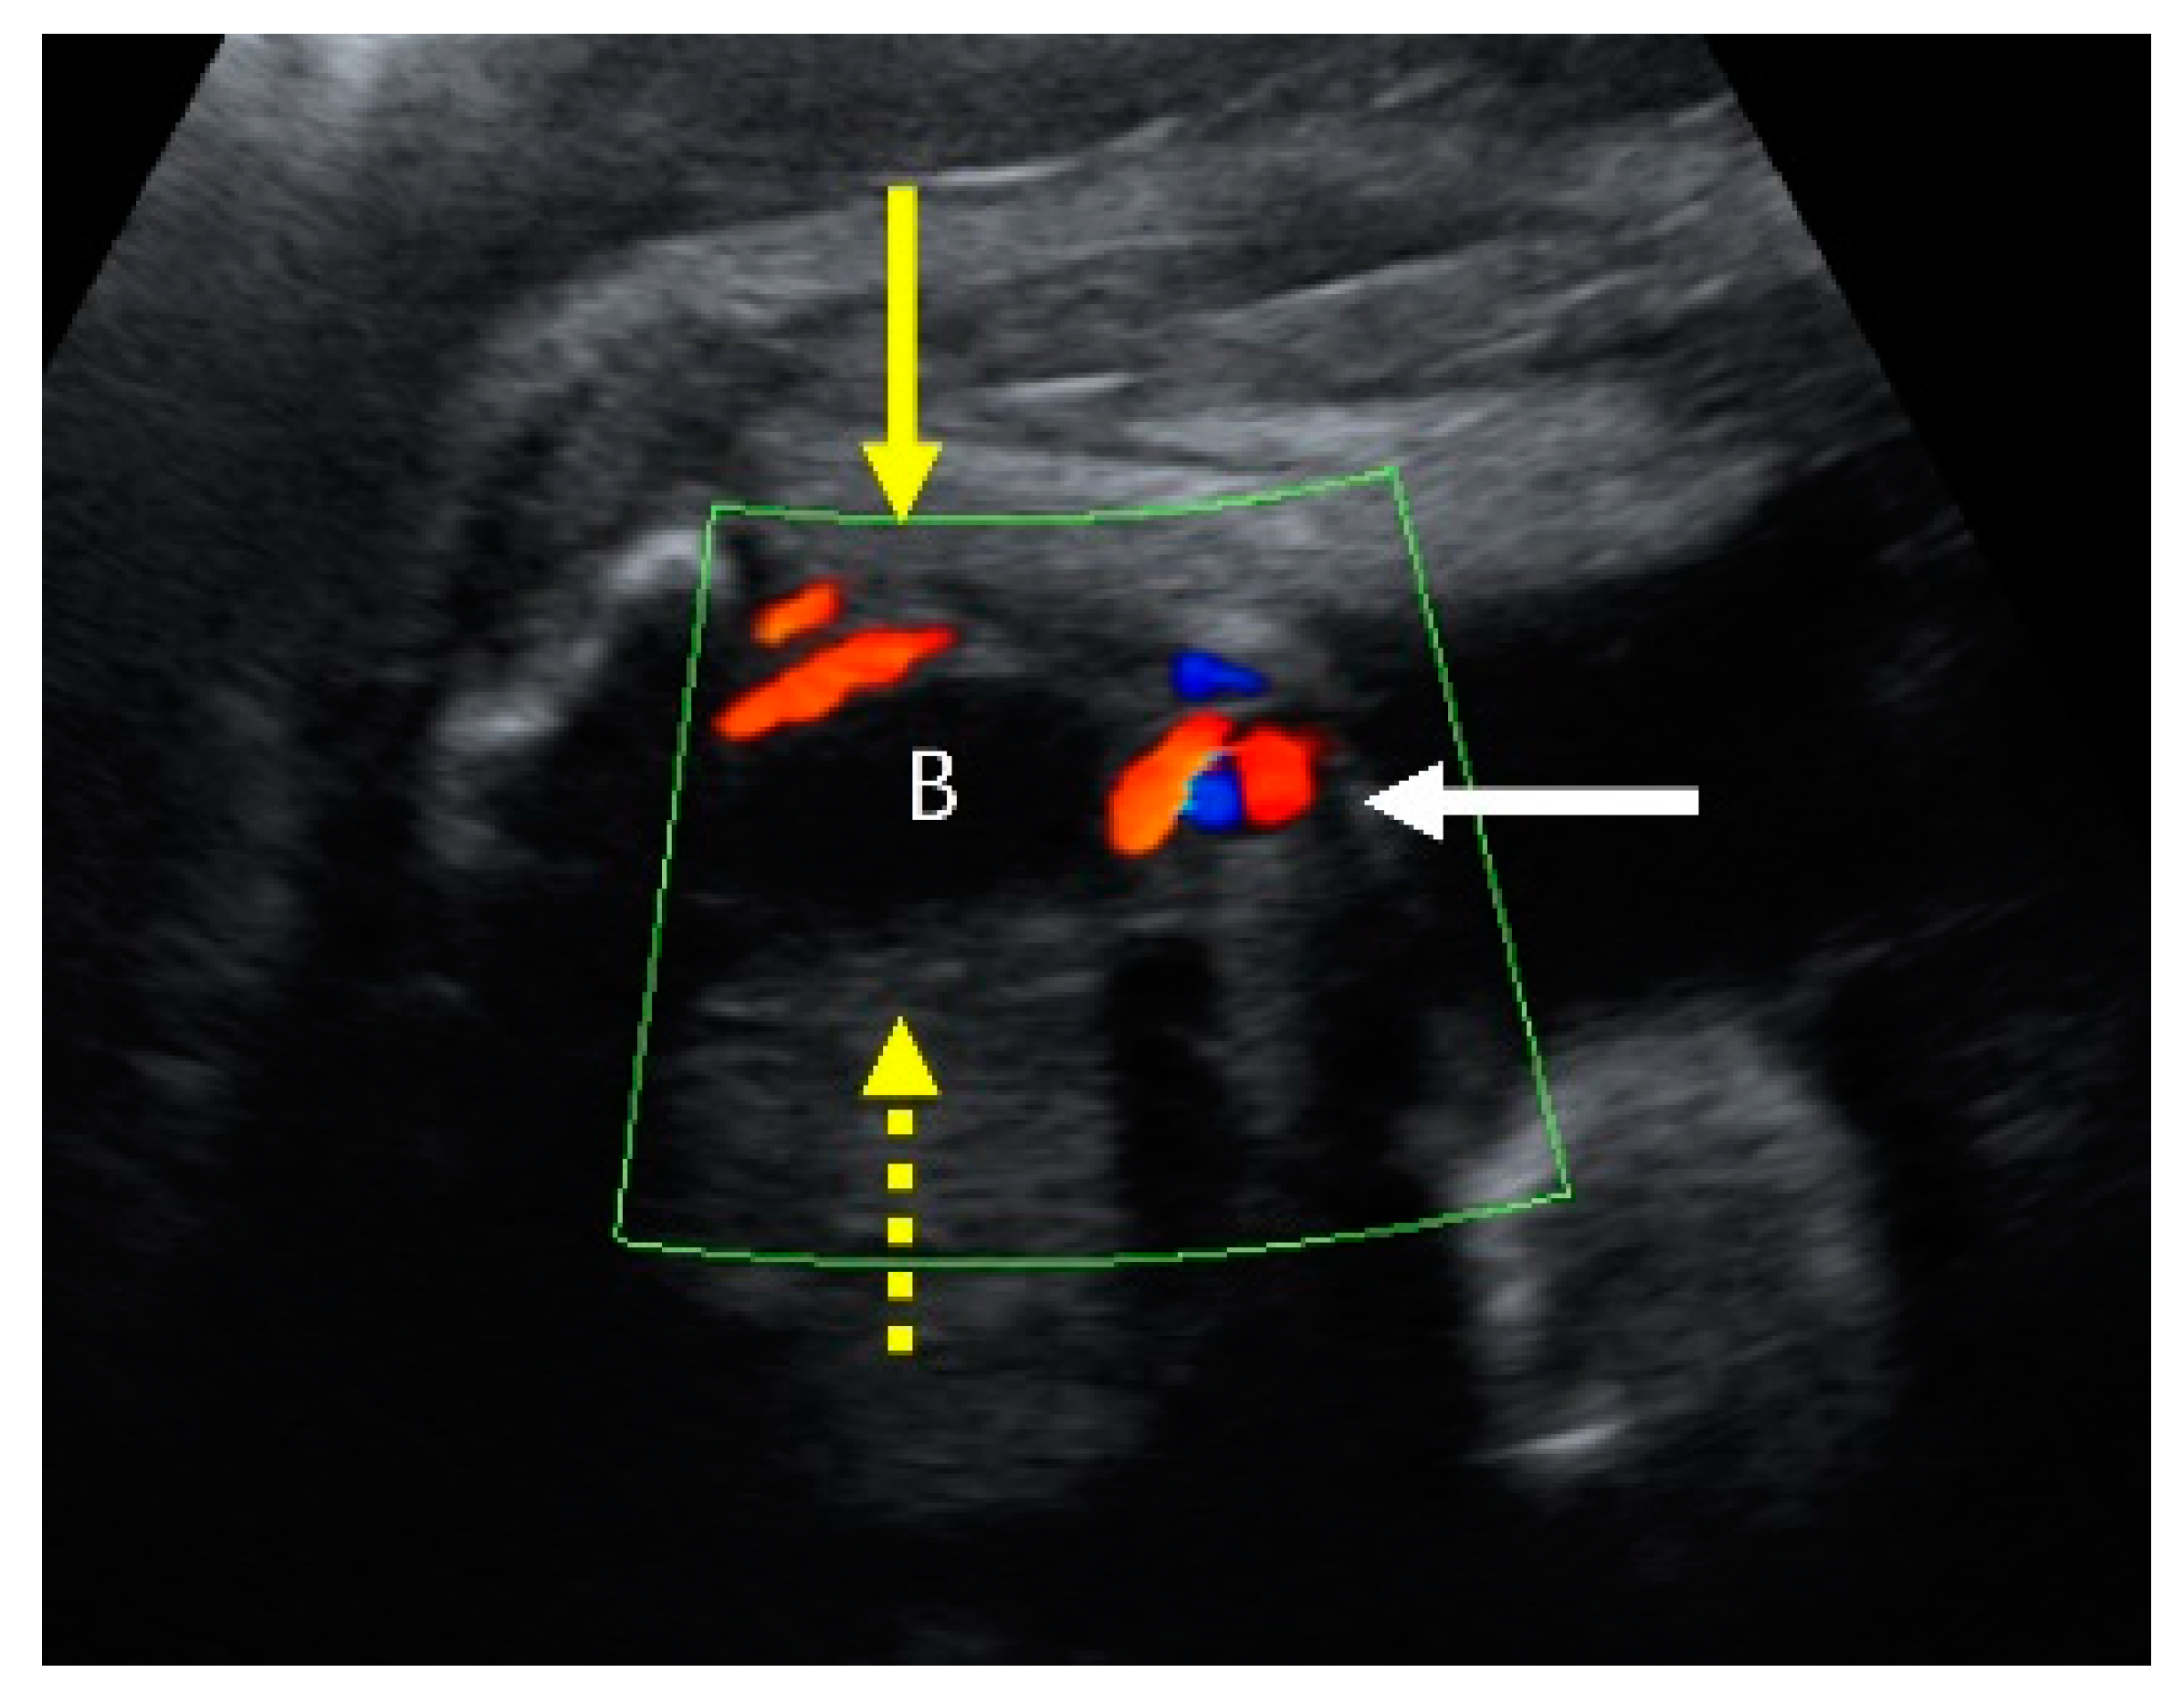

Fetus A’s right kidney was located in the normal renal fossa. Although fetus A’s right kidney was relatively small, it showed normal corticomedullary differentiation without structural abnormalities. On coronal view exams using color Doppler ultrasonography, we found only the right renal artery originating from the descending aorta. To rule out unilateral renal agenesis, we scrutinized the entire pelvic area and finally found the left kidney. However, the left kidney was also relatively small and displaced to an ectopic site almost adjacent to the bladder and near the midline of the body (Figure 4). A single umbilical artery was observed in fetus A (Figure 5).

Figure 5. A transverse view of prenatal ultrasonography at 31 + 1 weeks’ gestation shows a single umbilical artery (SUA) of fetus A. Color Doppler shows the bladder section (B: bladder), with one side of umbilical artery (yellow arrow) and the other side missing (yellow dotted arrow). The white arrow indicates the umbilical cord, containing vessels.